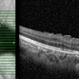

- toxocara granuloma

- Fundus photo showed central posterior granuloma on the optic nerve